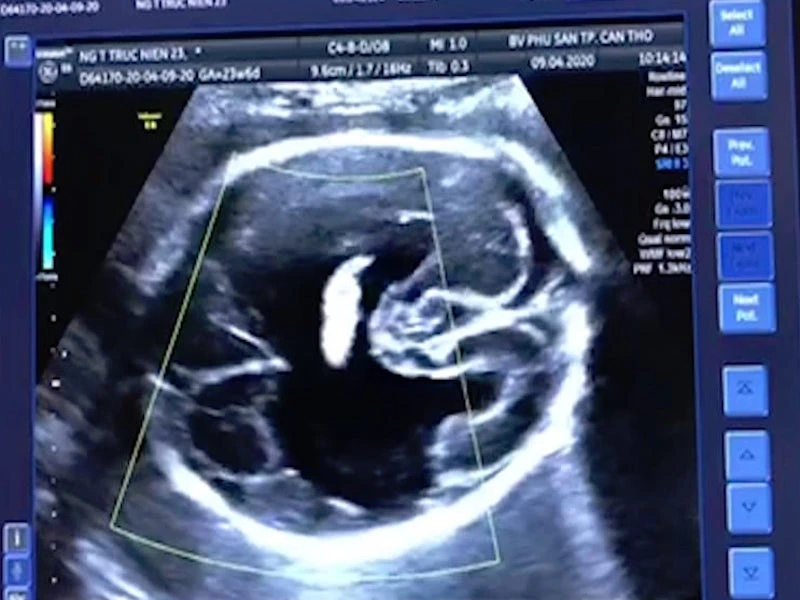

Ngày 11-9, Bệnh viện Phụ sản TP Cần Thơ cho biết các bác sĩ tại Trung tâm Sàng lọc - Chẩn đoán trước sinh và sơ sinh của BV vừa phát hiện trường hợp thai nhi có khe hở bất thường ở 2 bên bán cầu đại não. Khe này rất rộng, thông thương giữa khoang dưới nhện và não thất.

Trước đó, một thai phụ (23 tuổi) mang thai con so 24 tuần đến kiểm tra tại trung tâm. Qua thăm khám, bác sĩ phát hiện thai nhi bị dị tật chẻ não (Schizencephaly).

Hình ảnh siêu âm thai nhi. Ảnh: HẢI DƯƠNG